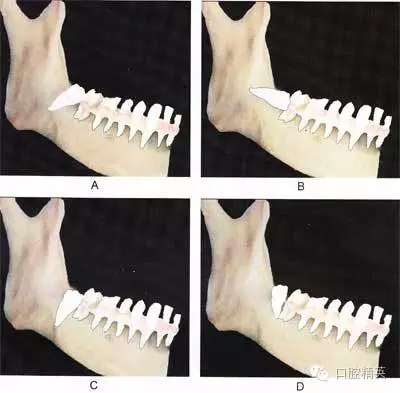

圖⒍1 根據(jù)第三磨牙牙體長軸與第二磨牙牙體長軸所成的角度不同可分為:近中 阻生(圖A):第三磨牙牙冠向近中傾斜;水平阻生(圖B):第三磨牙與第二磨牙牙體長軸相互垂直;垂直阻生(圖C):第三磨牙牙體長軸與第二磨牙平行;遠 中阻生(圖D):第三磨牙牙冠向遠中傾斜

A

B

C

圖6-2 根據(jù)阻生牙相對于下頜升支前緣位置關系分為:第1類 (圖A):下頜升支前緣和第二磨牙遠中面之間有足夠的間隙容 納第三磨牙牙冠;第2類(圖B):約一半的第三磨牙牙冠被下 頜升支前緣覆蓋;第3類(圖C):第三磨牙全部位于下頜升支 前緣內